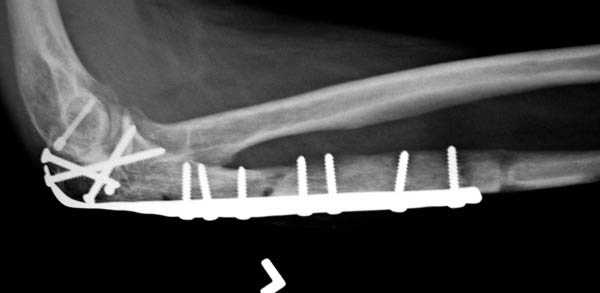

Снимки вот еще какие есть (наши лаборанты пытались сделать что то)

Good day dears colleagues! You presentated only one x-ray proection - lateral- of elbow.Accorden this I thing that this isn't avulsion fracture of olecranon,as usually can to see.This is Monteggia like fracture with subluxation of radial head.If

you can show AP x-ray or more more better CT elbow

I will more sure.Any way more imported of all normal long of ulna.So my recomendation ORIF proximal ulna by LCP - allow normal long by bridging, without attention to continues cortex but attention to articular surfase. On operation examen of radial head,becouse my sence isn't without damage.Operation by standart approach.

Снимок, действительно, "не очень". Но глядя на него почему-то возникает очень сильное ощущение, что там и венечный отросток сломан тоже. Что ситуацию здорово усложняет. Причём перелом венечного "III типа" - очень крупный фрагмент, отломанный под самое его основание. А это (без фиксации) уже грозит задней, а возможно - и фронтальной (вальгусной/варусной) нестабильностью.

Это не перелом локтевого отростка! Безусловно сломан венечный отросток и, может оказаться, что и головка луча. Сложный перелом! Доступ задний, фиксация пластиной (LCP) и стягивающими винтами. Только не по Веберу! Положение больного на животе. ЭОП.

При самом большом к Вам уважении, Сергей Анатольевич, не соглашусь. У меня, после того, как добавили "прямой" снимок, сомнений не осталось. Венечный сломан наверняка. Но чтобы судить, насколько это критично для стабильности, нужно иметь строго боковую проекцию. И при этом помнить, что на него крепятся медиальные связки.

Прикрепляю снимок, где обведен фрагмент, несущий на себе венечный отросток (весь он смещён с этим фрагментом или частично - без качественной боковой проекции судить сложно), и отдельно на снимке обведено "ложе", от которого он сместился.